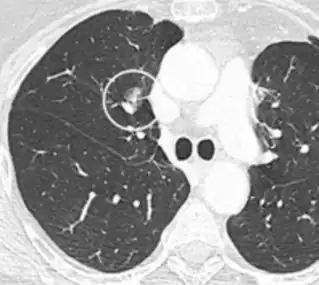

• Bubble-like lucencies in the nodule indicate cancer:[9]

• Vascular convergence is where vessels converge to a nodule without adjoining or contacting the edge of the nodule, and is mainly seen in peripheral subsolid lung cancers.[9] It reflects angiogenesis.[9]

Air bronchograms is defined as a pattern of air-filled bronchi on a background of airless lung, and may be seen in both benign and malignant nodules, but certain patterns thereof may help in risk stratification.[9]